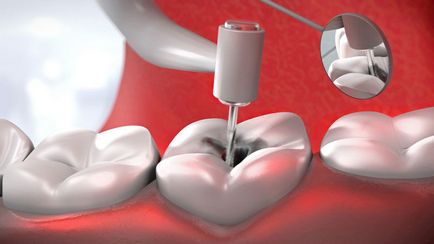

депульпірування зубів

Перший і найпростіший - депульпірування всіх опорних зубів. Його перевага - можливість видалення будь-якої кількості тканин опорних зубів і полегшення роботи лікаря-ортопеда і зуботехніка. Якщо лиття буде неточним, фахівця буде легше підточити зуб під установку коронки, ніж переробити коронку зуботехніка.

Другий варіант підготовки зубів до протезування - обійтися без депульпірованія опорних зубів, без наявності показань. Цей варіант протезування набагато складніше першого, так як вимагає певної акуратності і точності, а також деяких додаткових матеріалів.

Підточку здорових зубів проводиться з великою кількістю води, щоб уникнути перегріву зубного нерва. Процедура підточки проводиться під місцевою анестезією. Уникнути травмування зубного нерва під час підточки, дозволяють спеціальні наконечники і нові зубні бори.